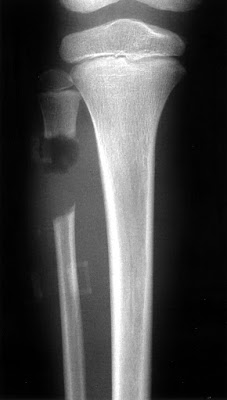

Μια νέα χειρουργική τεχνική που φιλοδοξεί να αντικαταστήσει τον γύψο ανέπτυξε Σκοτσέζος χειρουργός.

Μέσω της λαπαρασκόπησης εισάγεται στο τραύμα ένας μικρός συνδετήρας που λειτουργεί ως στήριγμα των τραυματισμένων συνδέσμων ή αρθρώσεων.

Ο συνδετήρας αυτός επιτρέπει στον ασθενή να κινείται και παράλληλα υποστηρίζει τους συνδέσμους μέχρι να επανέλθουν.

Η τεχνική αυτή έχει δοκιμαστεί σε περίπου 20 ασθενείς κι έχει παρατηρηθεί ταχύτερη ανάρρωση και λιγότερη δυσφορία, ενώ φαίνεται ιδιαίτερα ελκυστική στους αθλητές που δεν μπορούν να μείνουν για μεγάλο χρονικό διάστημα μακριά από τους στίβους.